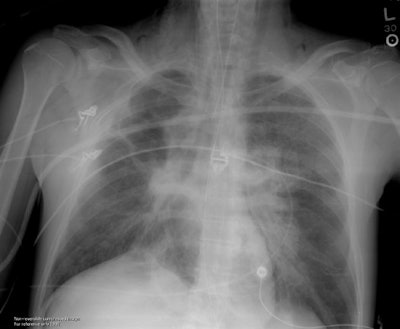

Pneumocardia:

Pneumocardia is a condition which is obviously incompatible with life. The CXR in this case was performed during a resuscitation attempt in a patient with a history of prior lung cancer (post radiation therapy changes can be seen in the right hemithorax). During the resuscitation, pericardiocentesis was attempted and air was likely introduced into the heart during the procedure. The image is a rather dramatic example of pneumocardia. The right atrium is air filled and appears as a rounded area of radiolucency in the anticipated location of the right heart border. Air outlines trabeculations within the ventricular chambers. Air can be identified in the left common carotid artery (coursing superiorly in the left neck) and also in the left vertebral artery. The patient also demonstrates pneumopericardium (air outlines the entire heart) and linear collections of air in the right neck are suspicious for pneumomediastinum. There is a curvilinear collection of air seen laterally below the right hemidiaphragm, and one may also question the presence of pneumoperitoneum.